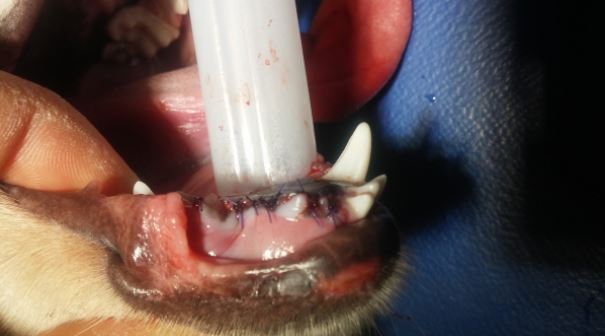

L’anesthésie générale avec intubation endotrachéale est essentielle. Elle prévient l’inhalation de l’aérosol bactérien (ou d’autres débris) ainsi que l’asphyxie par les liquides d’irrigation ou de refroidissement.

Un bourrage du pharynx est également recommandé - bien retirer ce bourrage avant l’extubation.

*L’extraction fermée peut être définie comme une avulsion sans retrait d’os alvéolaire. La cavité d’extraction est soit laissée ouverte pour une cicatrisation par granulation soit fermée en suturant la gencive au dessus de l’alvéole pour obtenir une cicatrisation par première intention.

*L’extraction ouverte ou chirurgicale se caractérise par le retrait d’une partie de l’os alvéolaire se trouvant au dessus de la racine dentaire pour faciliter l’extraction de la dent. La cavité d’extraction est ensuite suturée pour une cicatrisation par première intention.